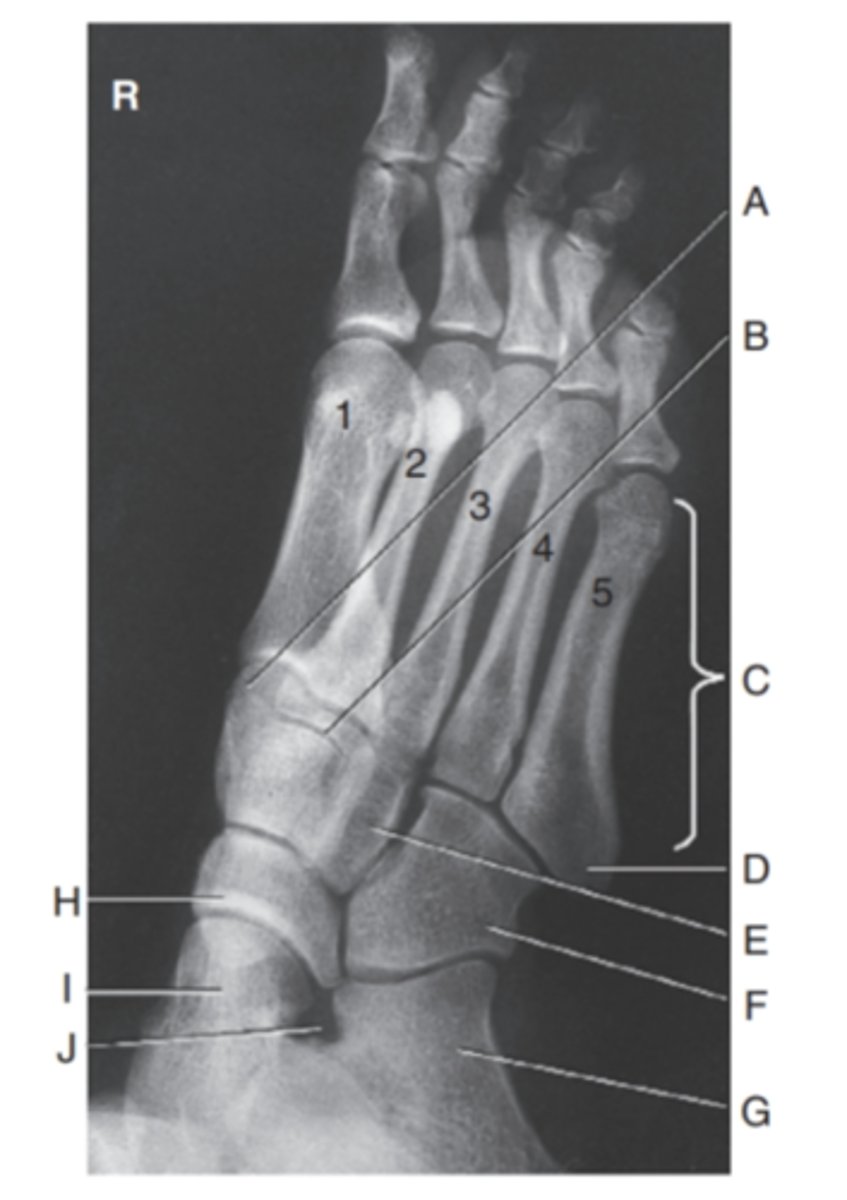

(AP OBLIQUE FOOT) what is A?

medial cuneiform

what is B?

intermediate cuneiform

what is C?

metatarsals

what is D?

Tuberosity (of the fifthmetatarsal

what is E?

lateral cuneiform

what is F?

cuboid

what is G?

calcaneous

what is H?

navicular

what is I?

talus

what is J?

sinus tarsi